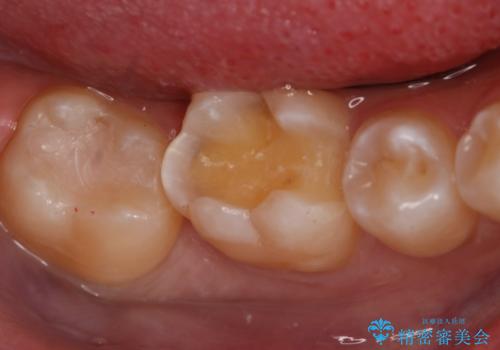

- 右上下6番の銀歯のやり変えを希望された患者様です。

切削量・形態を考慮し、上はセラミッククラウン、下はセラミックインレーでの治療を選択しました。

上はう蝕が歯頚部まで達していたのでクラウンでの治療を選択しました。

下はクラウンほど切削量が多くないと判断し、インレーでの治療を選択しました。